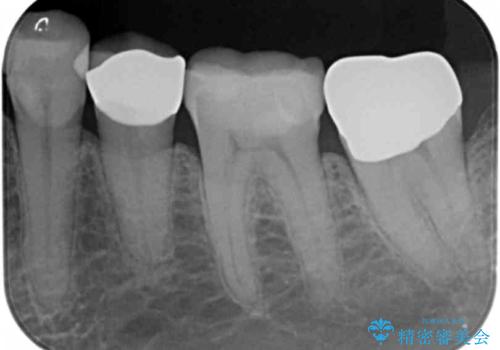

1. 昔いれたクラウンが割れたので金属の被せ物を入れたいの治療前